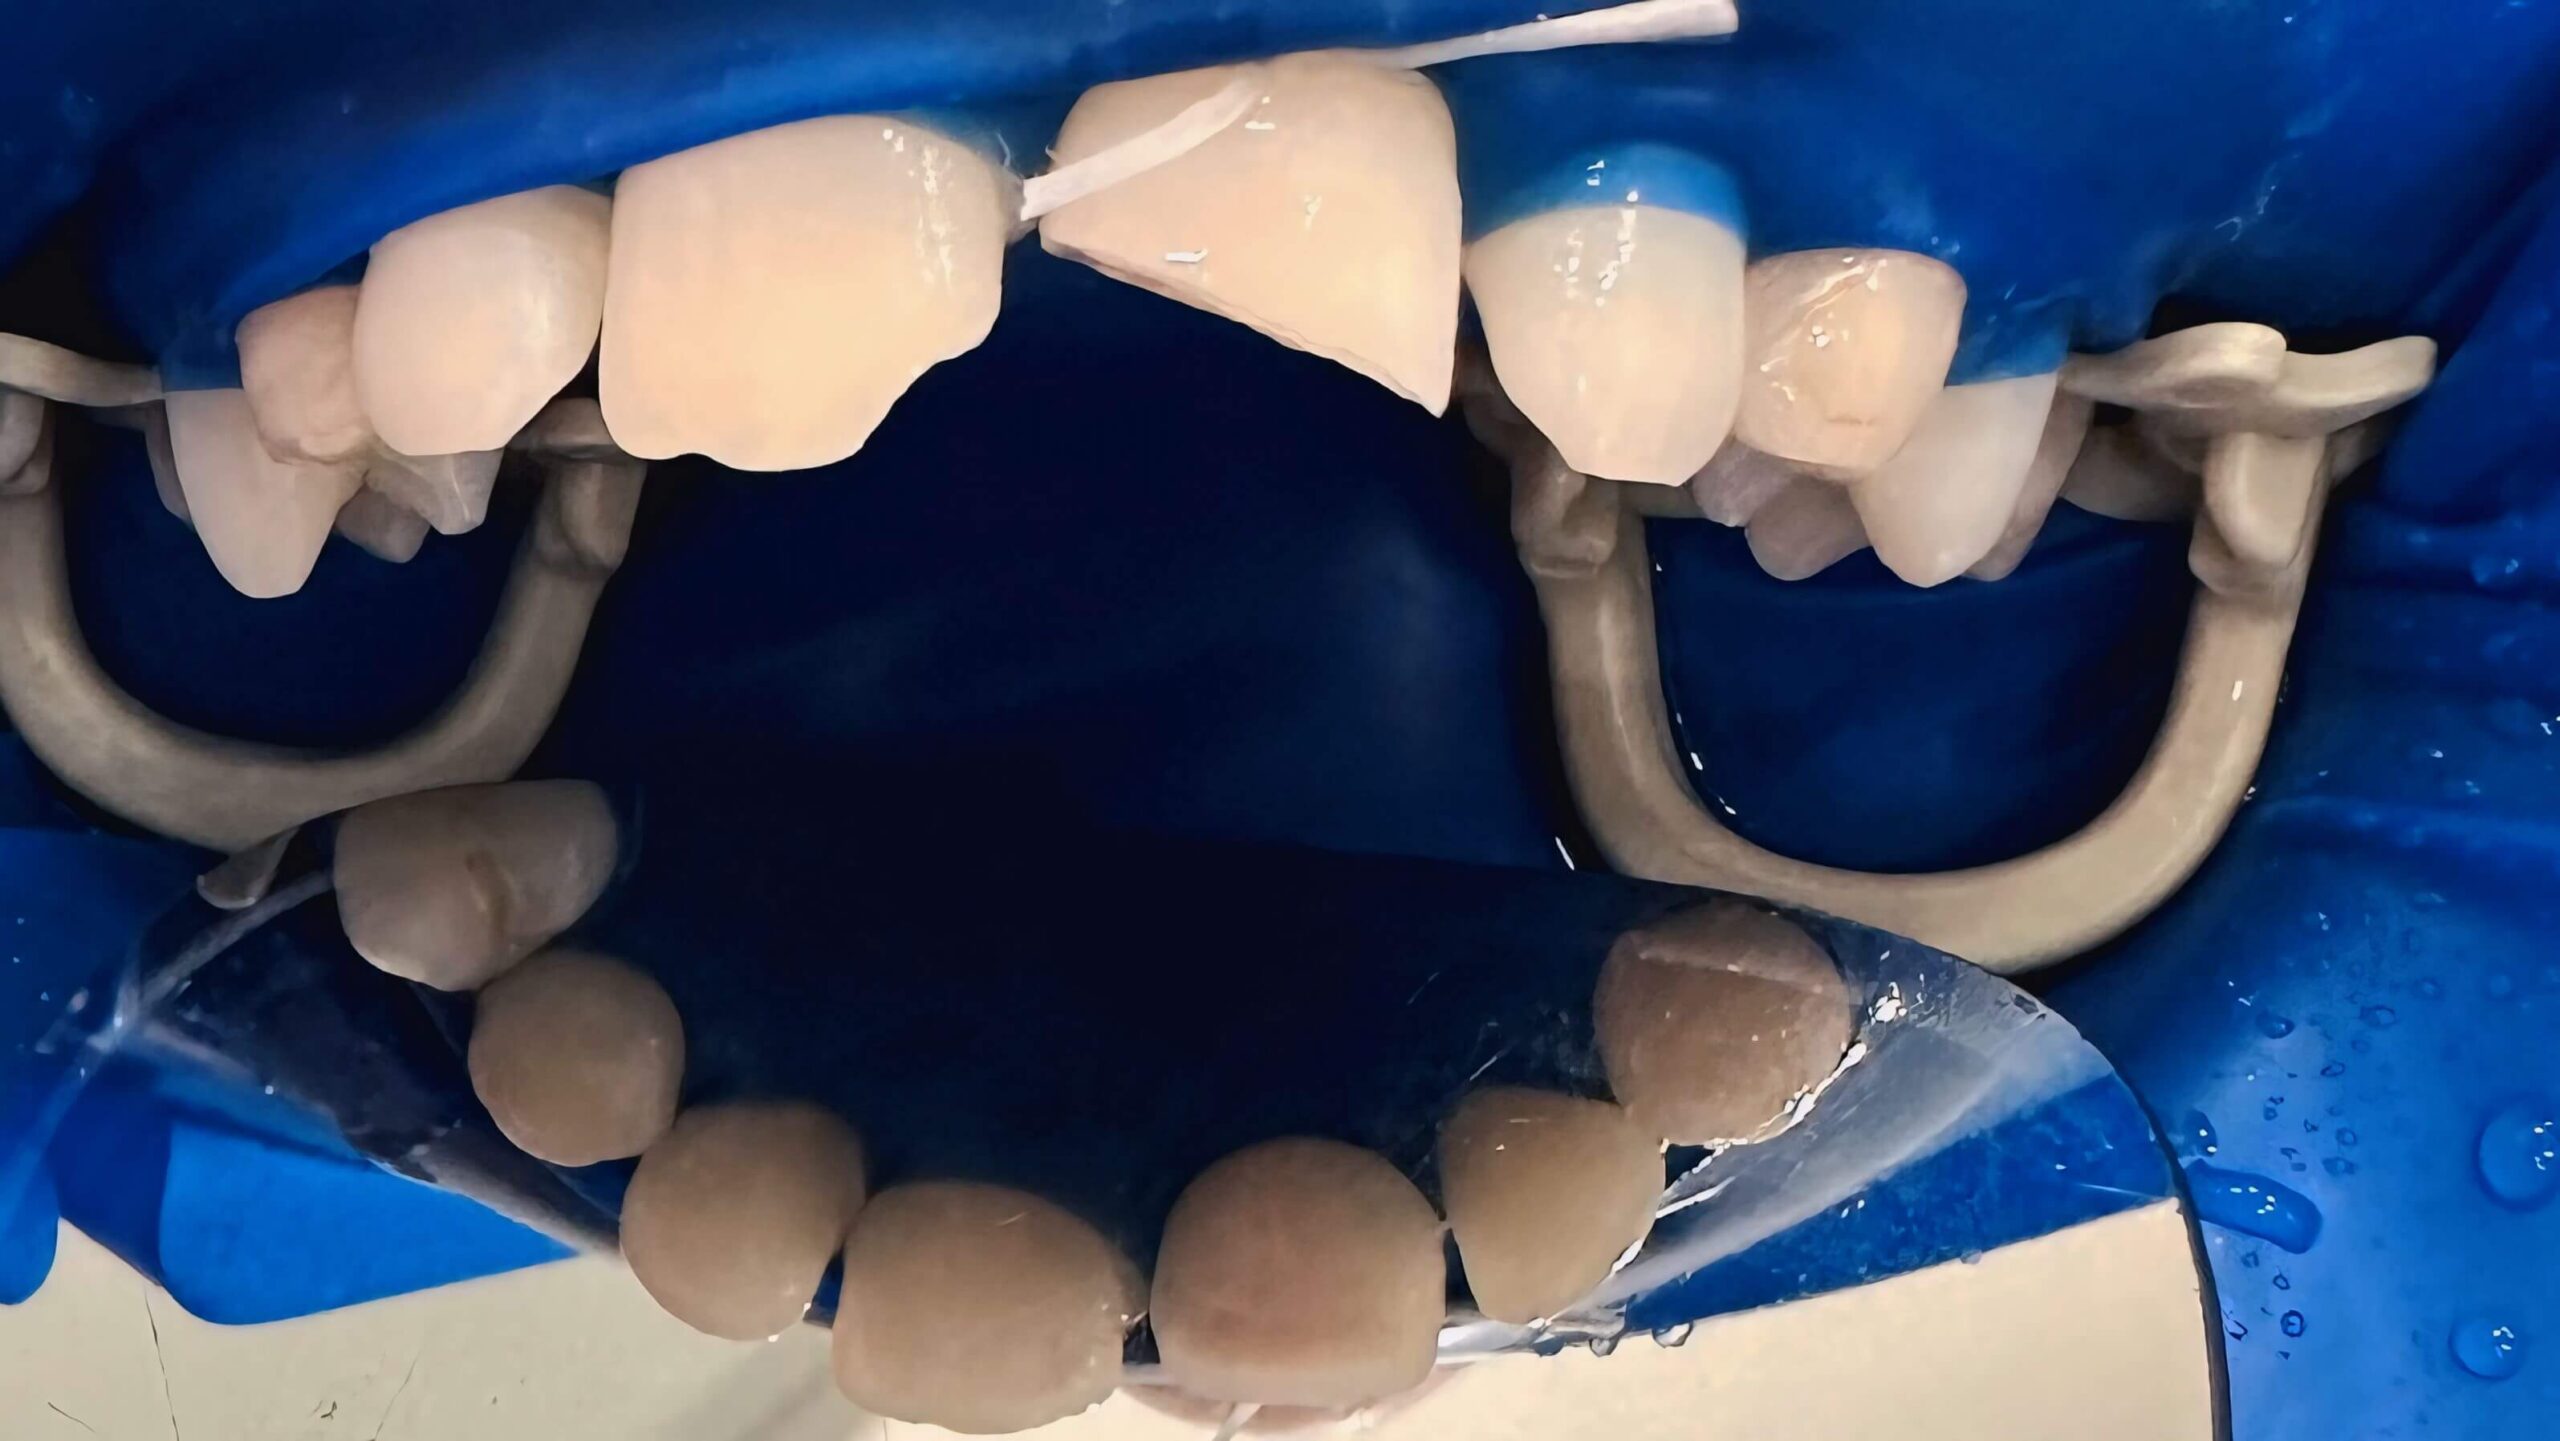

Протезування передніх зубів

Вихідна ситуація: потемніння передніх зубів, відсутність деяких зубів на верхній щелепі, що ускладнювало процес жування. Оцінивши стан залишкових зубів та ясен запропонували протезування передніх зубів. У результаті пацієнт отримав повністю відновлені передні зуби, які виглядають та функціонують як натуральні, що покращило його зовнішній вигляд та повернуло впевненість у собі й комфорт у спілкуванні.

Категорія: Ортопедія (протезування)